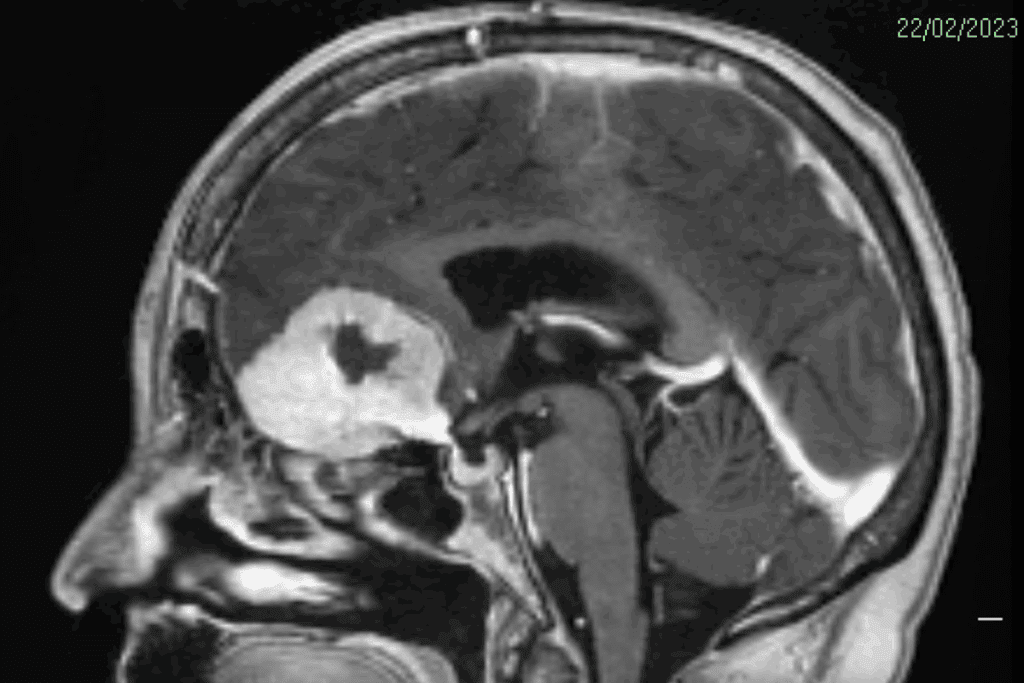

MRI Scans

Magnetic Resonance Imaging (MRI) is a top tool for finding these tumors. It gives clear pictures of soft tissues, helping to tell different tumors apart.

MRI is key for visualizing the tumor. It helps assess its size and location for treatment planning.